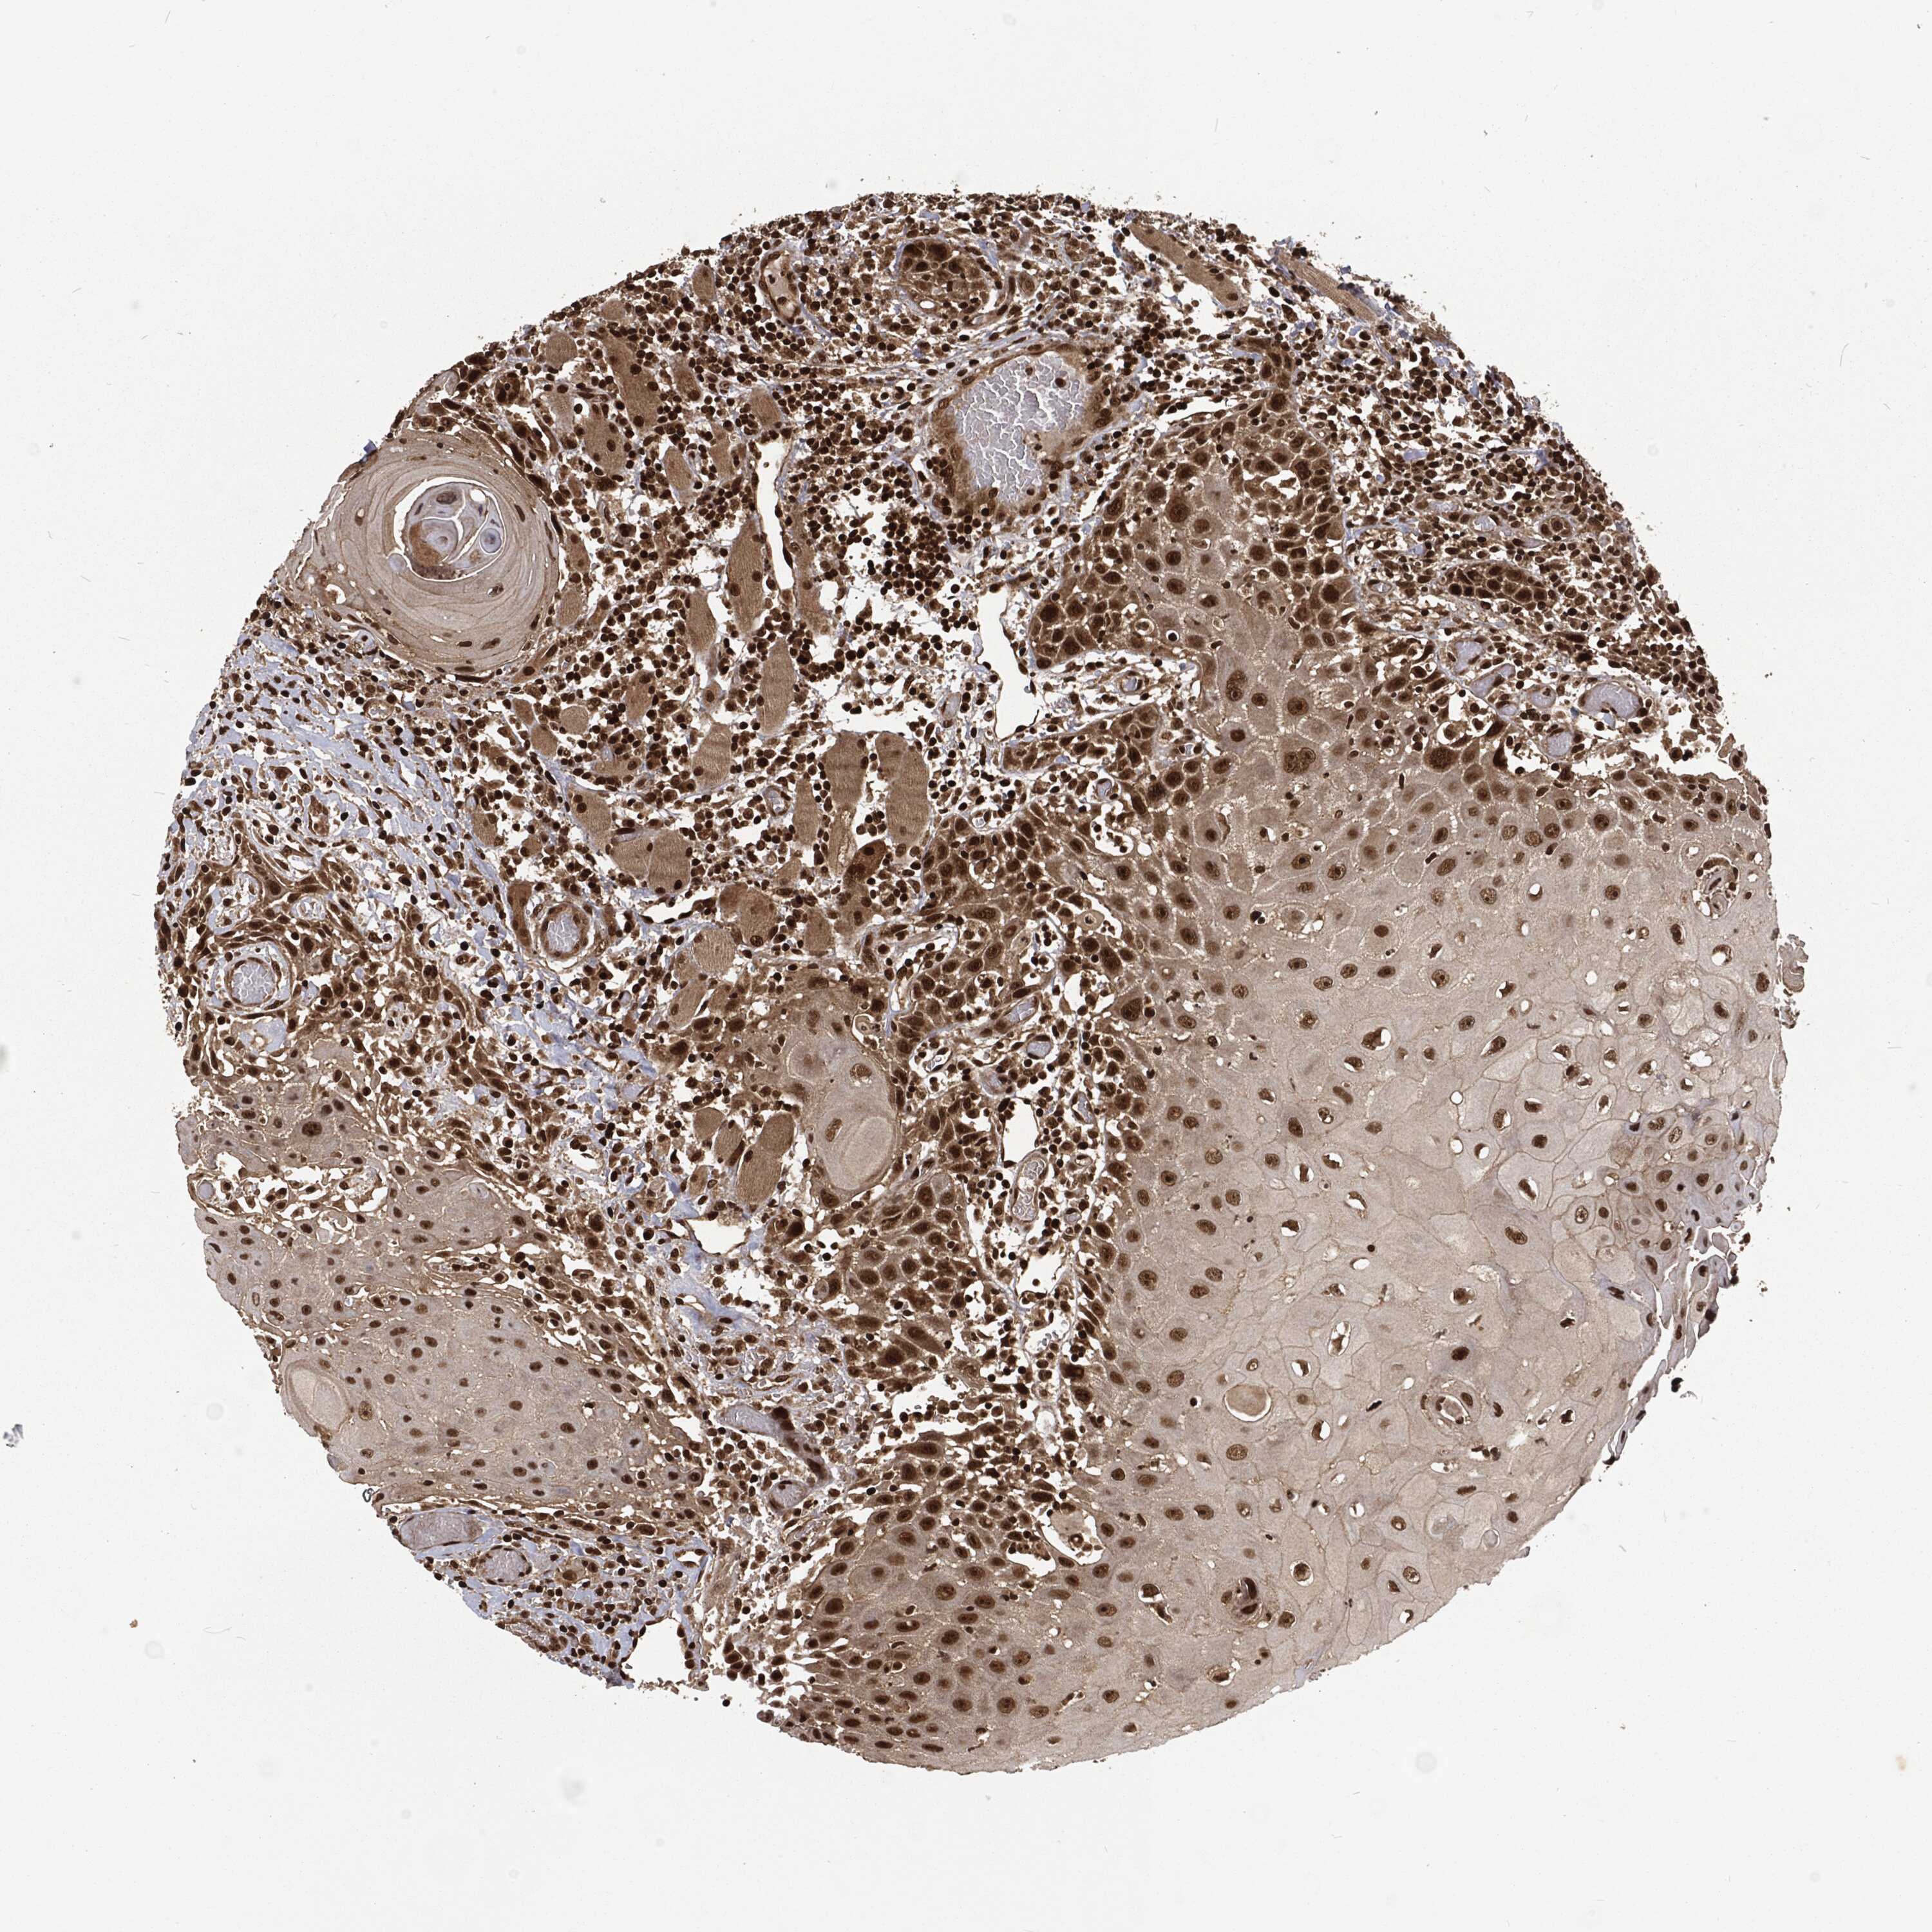

HEAD AND NECK CANCER - Protein expressioni

A mouse-over function shows sample information and annotation data. Click on an image to view it in a full screen mode. Samples can be filtered based on level of antibody staining by selecting one or several of the following categories: high, medium, low and not detected. The assay and annotation is described here.

Antibody stainingi

Antibody staining in the annotated cell types in the current human tissue is reported as not detected, low, medium, or high, based on conventional immunohistochemistry profiling in selected tissues. This score is based on the combination of the staining intensity and fraction of stained cells.

Each image is clickable and will lead to virtual microscopy that enables deeper exploration of all samples and also displays staining intensity scores, fraction scores and subcellular localization as well as patient and tissue information for each sample.

Antibody HPA076267

Staining

High

Medium

Low

Not detected

Intensity

Strong

Moderate

Weak

Negative

Quantity

>75%

75%-25%

<25%

None

Location

Nuclear

Cytoplasmic/membranous

Cytoplasmic/membranous,nuclear

Squamous cell carcinoma, NOS